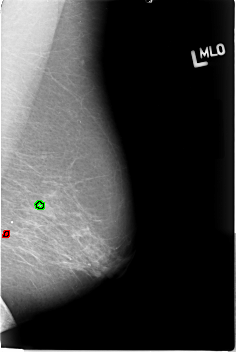

B_3015_1.LEFT_MLO

FILE: B_3015_1.LEFT_MLO.OVERLAY

TOTAL_ABNORMALITIES 2

ABNORMALITY 1

LESION_TYPE CALCIFICATION TYPE PUNCTATE-PLEOMORPHIC DISTRIBUTION CLUSTERED

ASSESSMENT 3

SUBTLETY 3

PATHOLOGY UNPROVEN

ABNORMALITY 2

TOTAL_OUTLINES 1